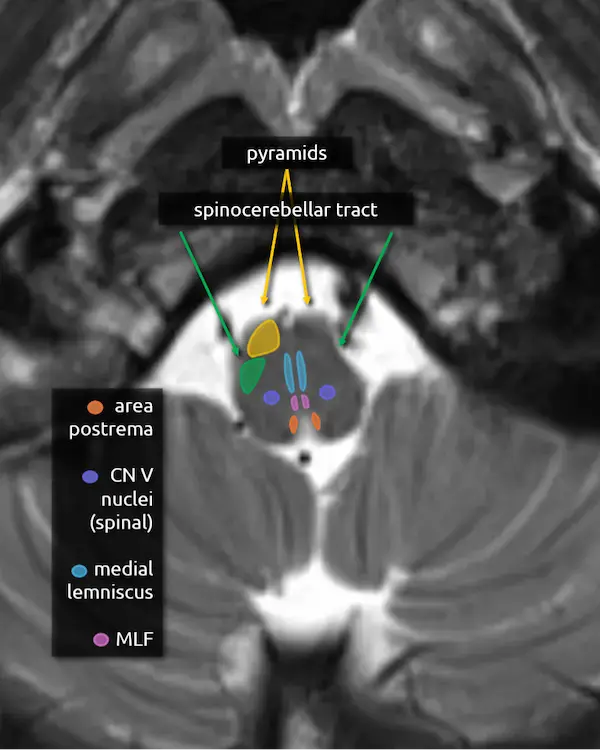

1. Pyramids:

The medullary pyramids contain the corticospinal tract and corticobulbar tract, which are sometimes collectively called the pyramidal tracts. They are named due to the shape they form on the ventral surface of the medulla, which usually becomes more pyramid-like inferiorly.

2. Spinocerebellar tracts:

The spinocerebellar tracts are ascending tracts from the spinal cord to the cerebellum involved in proprioception of the trunk and lower limbs. They are separated into ventral and dorsal divisions; the dorsal division travels to the cerebellum via the inferior cerebellar peduncle and the anterior division goes through the superior cerebellar peduncle. To reach the superior cerebellar peduncle, the anterior spinocerebellar tract travels along the lateral margin of the corticospinal tract through the pons. The spinocerebellar tract is best approximated posterior to the pyramids in the mid to lower medulla, where the ventral and dorsal division remain together.

The upper limb equivalent of the spinocerebellar tract is the cuneocerebellar tract, which is smaller and located medially.

Lesions involving these tracts will cause ataxia.

1. Pyramids

2. Inferior cerebellar peduncles

3. Medial lemniscus

4. Medial longitudinal fasciculus (MLF)

5. Inferior olivary nucleus

The inferior olivary nucleus is located in the upper medulla just posterior to the pyramids. It is involved in motor coordination and is a main component of the dentatorubro-olivary pathway (aka the triangle of Guillain and Mollaret), discussed below. A lesion that damages the predominantly inhibitory interneurons in the tracts connecting the corners of the triangle may result in disinhibition of the inferior olivary nucleus, characteristically but rarely manifesting as palatal myoclonus. Over time, the inferior olivary nucleus may swell, become T2 hyperintense, and eventually atrophy, a process called hypertrophic olivary degeneration.